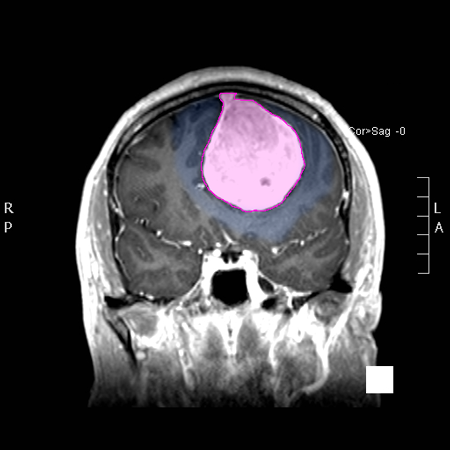

Διάγνωση Απαραίτητα είναι: Η λεπτομερής λήψη ιστορικού και η κλινική εξέταση, Η μαγνητική τομογραφία του εγκεφάλου με σκιαγραφικό, Σε ορισμένες περιπτώσεις: Η μαγνητική αγγειογραφία ή/και φλεβογραφία του εγκεφάλου, Η μαγνητική τομογραφία του εγκεφάλου με σκιαγραφικό για νευροπλοήγηση, Ηλεκτροεγκεφαλογράφημα και άλλες εξειδικευμένες εξετάσεις όπως μέτρηση οπτικής οξύτητας και οπτικών πεδίων προτείνονται κατά περίπτωση. |

Θεραπεία Η θεραπεία των μηνιγγιωμάτων που προκαλούν συμπτώματα είναι κατά κανόνα χειρουργική, και αυτό γιατί αποτελεί τον πλέον άμεσο και αποτελεσματικό τρόπο να αποσυμπιεστεί ο εγκεφαλικός ιστός ή τα κρανιακά νεύρα τα οποία πιέζονται. Στα ασυμπτωματικά μηνιγγιώματα η θεραπευτική σύσταση γίνεται ανά περίπτωση και η απόφαση εξαρτάται από πολλούς παράγοντες, όπως η ηλικία του ασθενούς, το μέγεθος και η θέση του μηνιγγιώματος, τα απεικονιστικά χαρακτηριστικά του, οι πληροφορίες που υπάρχουν από παλαιότερες απεικονίσεις για το ρυθμό ανάπτυξής του, κα. Όταν η θέση των μηνιγγιωμάτων ή η γενικότερη υγεία του ασθενούς δεν επιτρέπει ασφαλή χειρουργική παρέμβαση, τότε μπορεί |